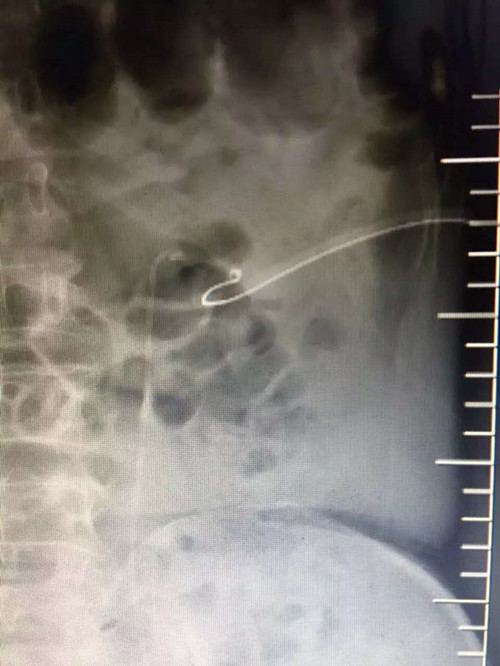

泌尿外科手术效果图